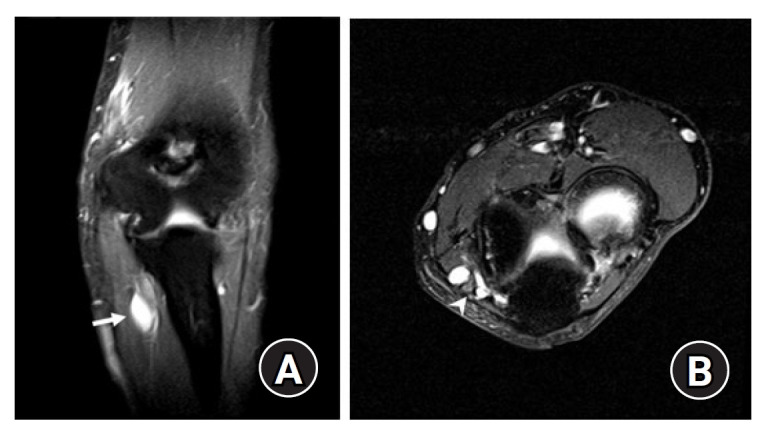

眶管综合征是指肘部周围尺神经通路受压引起的压迫性神经病。一名 63 岁的男性患者前来就诊,主诉其左手无名指和小指感觉减退和无力,并称症状最早出现在 6 个月前。大约 5 年前,他在蒙古接受了切除左肘关节神经节囊肿的手术。磁共振成像显示,之前的手术部位有一个囊性肿块,压迫了肘管内的尺神经。患者接受了尺神经减压术和前方转位术,并切除了囊性肿块。经病理检查,肿块被诊断为神经节囊肿。随访一年后,患者的感觉功能障碍和乏力等症状有所改善。本报告描述了一例罕见的神经节囊肿复发病例,该病例曾接受过神经节囊肿切除术,但复发后压迫了肘隧道内的尺神经。

Cubital tunnel syndrome refers to compression neuropathy caused by pressure on the ulnar nerve pathway around the elbow. A 63-year-old male patient visited the clinic complaining of decreased sensation and weakness in his left ring finger and little finger, stating that the symptoms first began 6 months prior. He had undergone surgery to remove a ganglion cyst from his left elbow joint about 5 years prior in Mongolia. Magnetic resonance imaging revealed a cystic mass located at the previous surgical site, which was compressing the ulnar nerve within the cubital tunnel. Ulnar nerve decompression and anterior transposition were performed, and the cystic mass was excised. Upon pathological examination, the mass was diagnosed as a ganglion cyst. The patient's symptoms including sensory dysfunction and weakness improved over the 1-year follow-up period. This report describes a rare case of ganglion cyst recurrence compressing the ulnar nerve in the cubital tunnel after previous ganglion cyst excision.